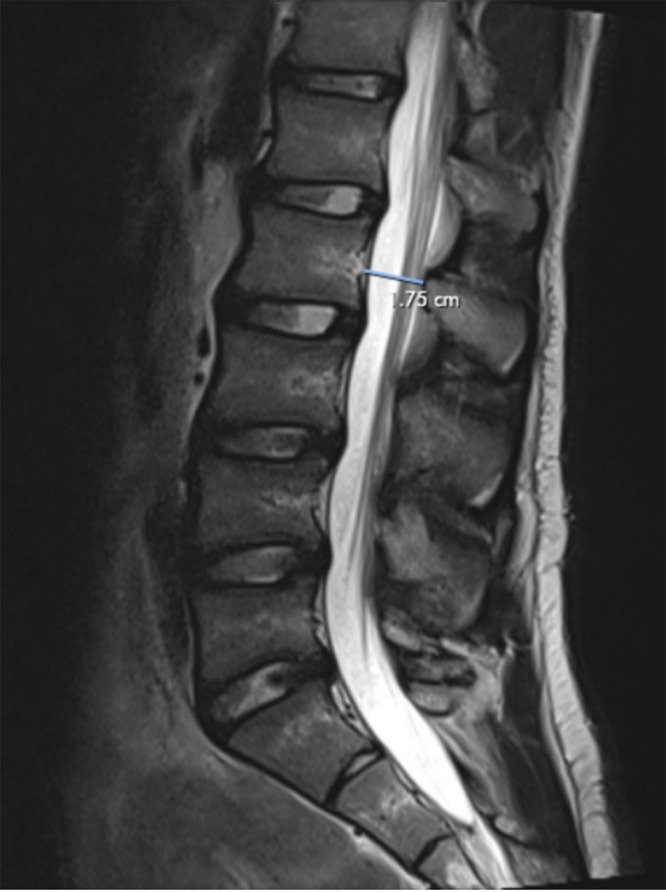

Observations: In this case, the Castellvi classification system failed to identify the patient (with 2 years of back and L5 pain) as having an LSTV, even though he displayed LSTV-like anatomy because both L5 transverse process heights measured less than 19 mm. He attained brief but significant relief from bilateral injections into the L5-S1 transverse/ala region and underwent a minimally invasive bilateral decompression of L5-S1 with almost complete relief of his symptoms maintained more than 6 months postoperatively.